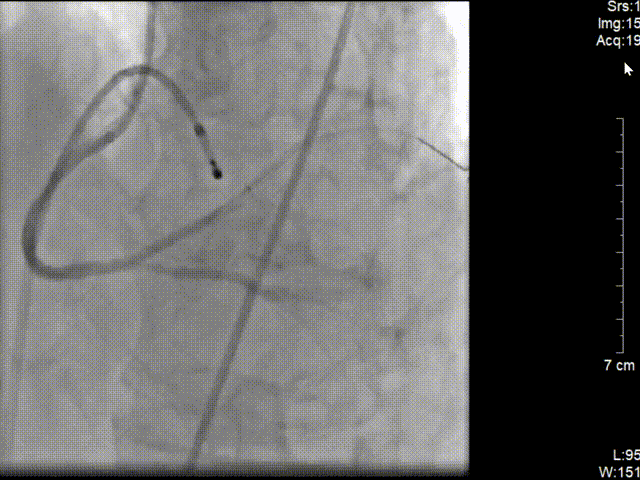

C.立即穿刺股静脉行临时起搏器植入;

D. 时间急迫,穿刺股动脉建鞘行急诊PCI;

在J型导丝指引下6F JR4.0指引导管于右冠口,行造影提示右冠近段急性闭塞,将SION blue导丝操作通过右冠近端闭塞处并达远段真腔,予2.0*15预扩张球囊行病变处预扩张处理,复查造影可见血栓,予血栓抽吸导管反复抽吸,抽出大量红色血栓。